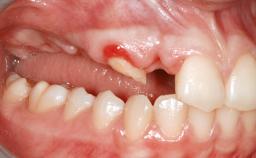

An 18-year-old man was referred for implant therapy in the posterior mandible to the Department of Oral Surgery and Stomatology (University of Bern, Switzerland). He was healthy and did not smoke. Tooth 35 was congenitally missing, involving a single-tooth edentulous space that offered an adequate mesiodistal dimension for implant placement but exhibited a typical pattern of buccal flattening. A panoramic radiograph was obtained, which revealed a sufficient vertical bone height above the mandibular canal and a normal bone structure in the edentulous area.

Bone Volume Horizontally and vertically sufficient Horizontally deficient Deficient vertically or deficient vertically AND horizontally

Bone Volume Deficient horizontally, requiring prior grafting